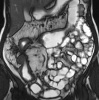

MRI of the intestine.

МРТ кишечника использовалась в медицинской практике уже несколько десятилетий. Это относится к числу высокоинформативных методов. Это осуществляется за счет изменения пространственной ориентации протонов водорода в магнитном поле и записи данных с последующей передачей на специальный компьютер. Может быть назначен гастроэнтерологами и хирургическими специалистами, а также онкологами. Исследование проводится реже, чем другие диагностические процедуры, из-за высокой стоимости и ограниченного количества показаний. Основная часть кишечных заболеваний, в том числе опухоли, выявляется клинически и с помощью других методик. МРТ кишечника обычно проводится при подозрении на патологию тонкой кишки, которая недоступна для исследования рентгеноконтрастным и эндоскопическим методами (за исключением дорогостоящей и все еще редко используемой капсульной эндоскопии).